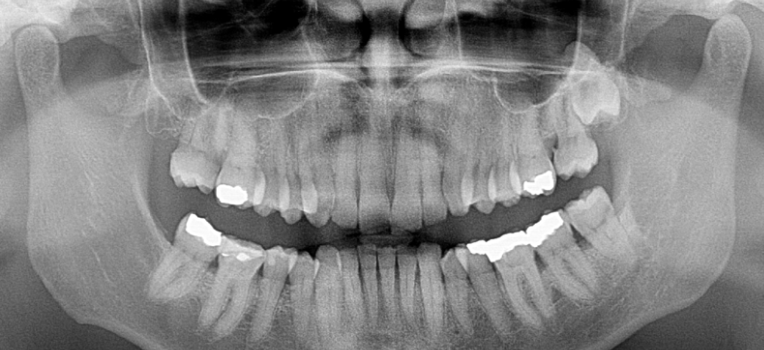

Panoramic imaging is essential baseline assessment. The CS 8100 panoramic provided the full picture — root morphology, periodontal status, TMJ assessment, and detection of any undiagnosed pathology — before appliance therapy began. You cannot safely fit an MAD without this information.

Carestream CS 8100

Extraoral panoramic imaging system providing the essential baseline assessment — root morphology, periodontal status, TMJ, and pathology screening before appliance therapy.